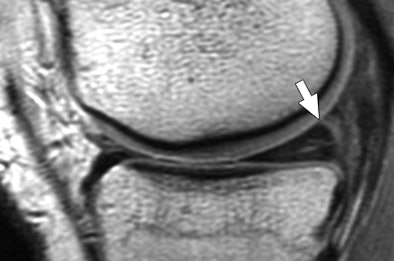

| Thirty-six-year-old man who had injured his knee while squatting down with true-positive MR diagnosis of medial meniscal tear at meniscocapsular junction on MRI 21 days after injury; tear was confirmed at arthroscopy 30 days after injury. Anterior cruciate ligament tear was not identified. Sagittal proton density-weighted (above) and T2-weighted (below) images show linear intermediate-signal-intensity line (arrow in above image) and intermediate- and less-than-fluid-intensity line (arrow in below image) contacting superior surface of meniscus. Fig. 2a, b. De Smet AA, Nathan DH, Graf BK, Haaland BA, Fine JP. Clinical and MRI findings associated with false-positive knee MR diagnoses of medial meniscal tears. AJR. 2008;191(1):93-99. Images courtesy of the American Journal of Roentgenology and the American Roentgen Ray Society. |